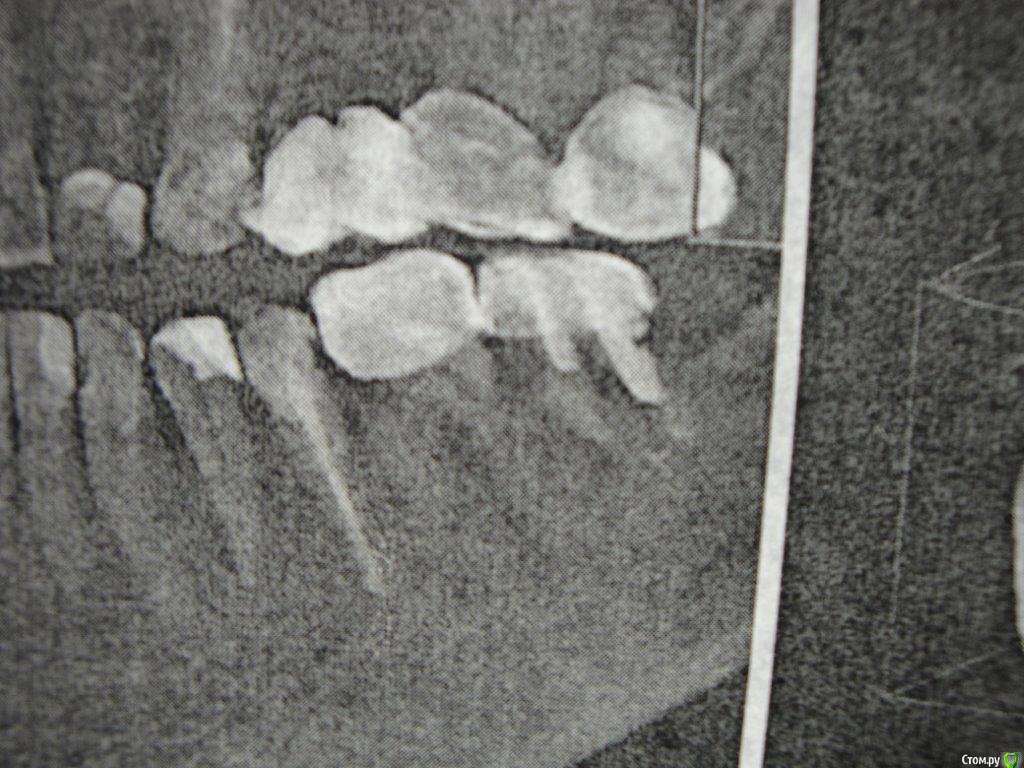

Коша Опубликовано 26 апреля, 2016 Поделиться Опубликовано 26 апреля, 2016 Здравствуйте!Подскажите пожалуйста!можно ли восстановить 7снизу слева зуб. пару врачей мне сказали, что нужно удалять, но вера в современную стоматологию, еще теплит надежду, что возможно еще можно над ним поработать, и пока оставить его!Зуб не болит, я им жую, но стала образовываться щель между телом зуба и краем коронки.Есть несколько снимков (отрывки с панорамных снимков)- прилагаю их. Ссылка на комментарий